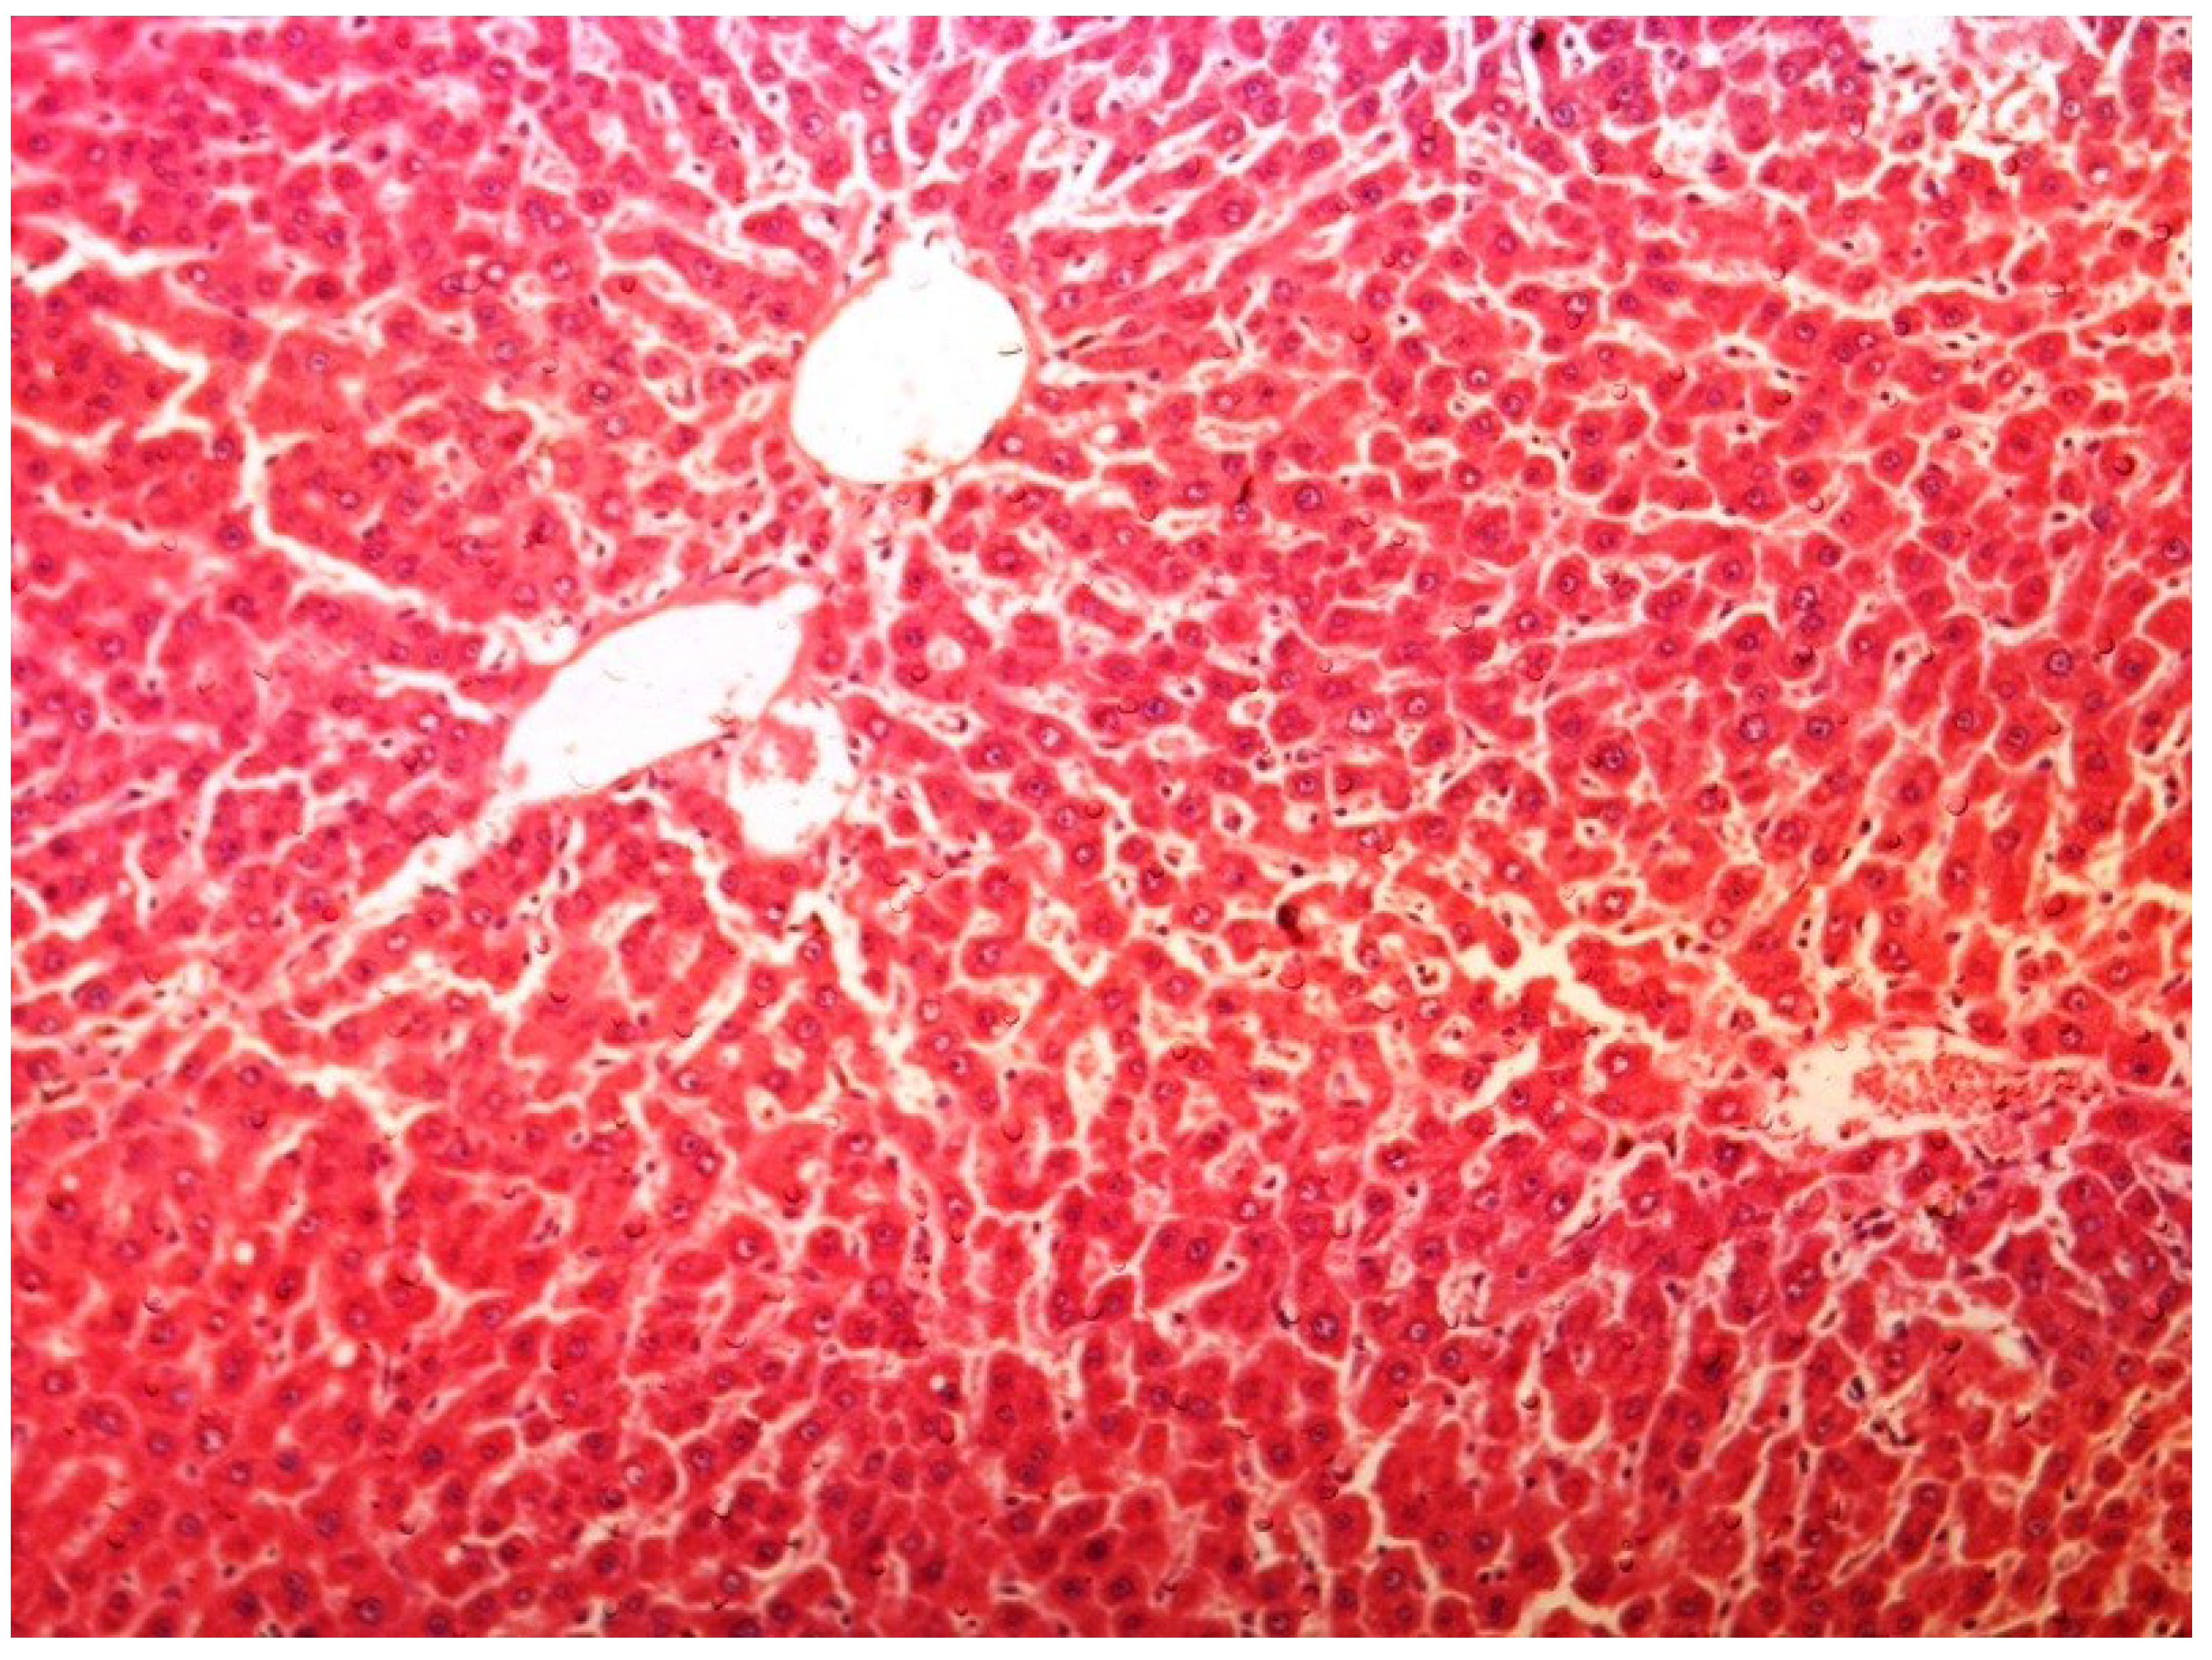

2.11. Histopathology